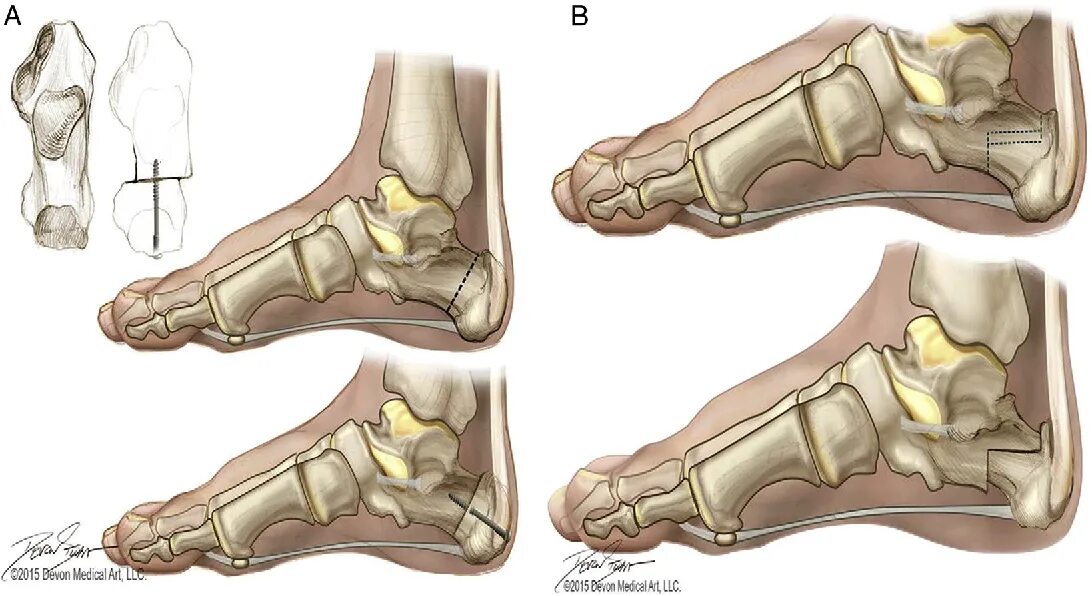

Пяточная остеотомия